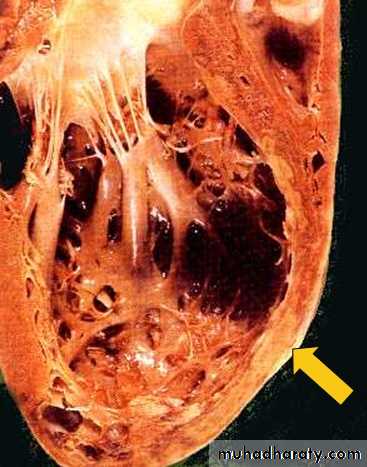

A hemorrhagic zone of rupture is located in the center of the image. On one side of the rupture channel is a region of almost transmural myocardial infarction with a central zone of coagulative necrosis. On the other side of the rupture channel is a zone of viable myocardium. Rupture often takes place where there is a sharp interface between normal and weakened necrotic myocardium.left ventricular aneurysm with thrombus - Gross, endocardial surface

The aneurysm is a large oval zone located toward the apex of the left ventricle. An aneurysm forms when a region of the left ventricular wall is weakened by infarction and then thinned by the constant pressure of systolic contractions. Aneurysms at any site are often areas of abnormal flow and thus are predisposed to thrombosis. The aneurysm in this case has been filled by an organizing thrombus. Left ventricular thrombi can generate systemic emboli. Ventricular wall aneurysms may also cause congestive heart failure and dangerous arrhythmias.This high power microscopic view of the myocardium demonstrates an infarction of about 1 to 2 days in duration. The myocardial fibers have dark red contraction bands extending across them. The myocardial cell nuclei have almost all disappeared. There is beginning acute inflammation